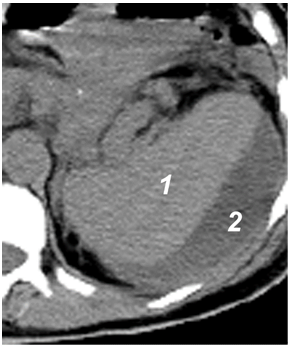

Эхографическая визуализация жидкости только в полости малого таза соответствует «малому» гемоперитонеуму, объем крови при этом не превышает 7,3 мл/кг массы тела (рис. 11).

Рис. 11. «Малый» гемоперитонеум: 1 – мочевой пузырь; 2 – кровь.

При «среднем» гемоперитонеуме, помимо малого таза, кровь эхографически определяется в печеночно-почечном кармане, латеральных каналах, периспленическом пространстве, ее объем колеблется от 7,6 до 25,8 мл/кг массы тела (рис. 12).

Рис. 12. «Средний» гемоперитонеум: 1 – печень; 2 – почка; 3 – кровь.

Нахождение жидкости еще и под передней брюшной стенкой в области мезогастрия соответствует «большому» гемоперитонеуму с объемом крови в брюшной полости более 26,7 мл/кг массы тела (рис. 13).

Рис. 13. «Большой» гемоперитонеум: 1 – петли тонкой кишки; 2 – кровь.